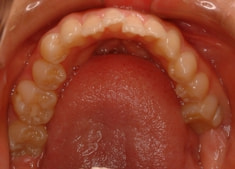

治療前